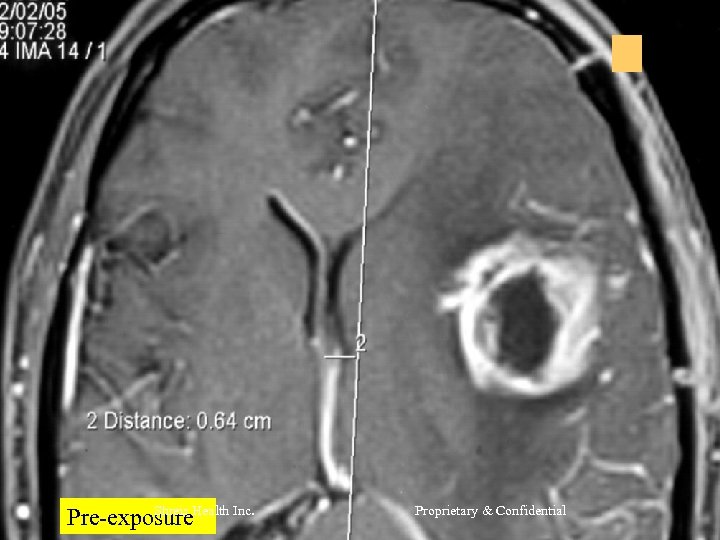

CASE 2 Mr R, 56 yrs l Nov 2004 – MRI Brain = Left frontal SOL (4 x 3 cm) - SX = Craniotomy x decompression of insular glioma HPR = Glioblastoma Grade IV l RT – 60 Gy/30 # till Jan 2005 l CT – Temedol x 2 # till Feb 2005 l Shreis Health Inc. Proprietary & Confidential

l l Presented Feb 05 - Loss of memory - Apathetic - Hemiparesis ® (power 3/5) Today after 1 course of RFQMR - No focal/Gen Neuro deficit - Normal higher functions and back to work. Shreis Health Inc. Proprietary & Confidential

Shreis Health Pre-exposure Inc. Proprietary & Confidential

Shreis Pre-exposure. Health Inc. Proprietary & Confidential